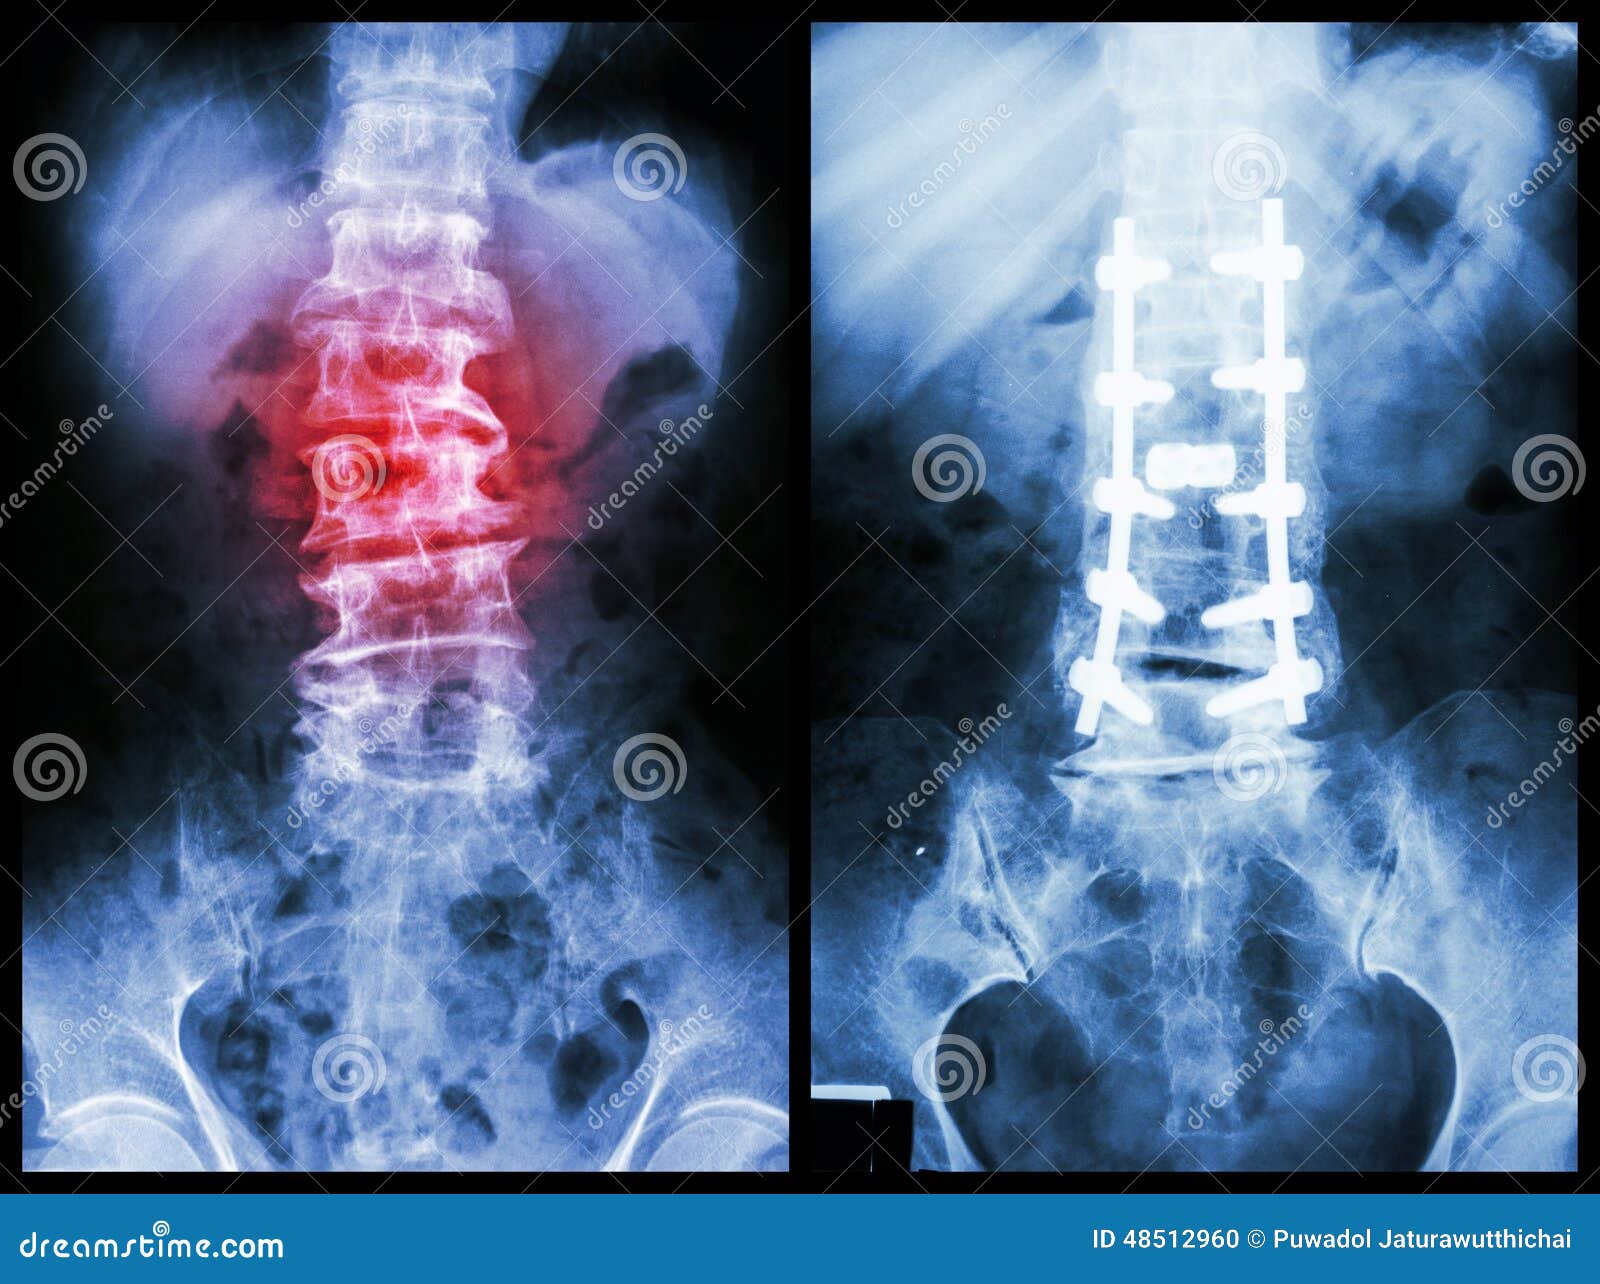

Spondylosis . Before And After Surgery . Stock Image CartoonDealer